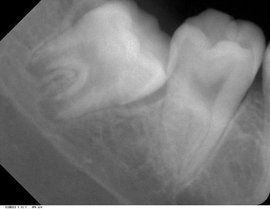

埋伏牙與其周圍組織之間存在牙囊組織,一般是無炎症的。埋伏牙有一種向牙齒胎面及切端方向移動的自然趨勢,遇到阻礙時則產生壓力。埋伏一段時間之後,牙冠釉質表面的成釉上皮會萎縮消失,其上可能有來自牙囊的牙骨質沉積。偶見埋伏牙的牙體組織發生置換性吸收,易誤認為齲齒。

埋伏牙臨床多見於第三磨牙,其次為上頜尖牙,第二雙尖牙和額外牙等,有時有雙側的埋伏牙。一般由X光片檢查發現。在上頜中切牙之間,常有額外牙埋伏,可使兩個中切牙之間間隙加寬。埋伏牙可對相鄰的牙齒產生壓迫症狀,如第二磨牙受埋伏的第三磨牙壓迫,發生牙根吸收,引起疼痛並繼發牙髓炎和根尖周炎。偶見多年戴總義齒的老年患者,有埋伏牙的萌出。